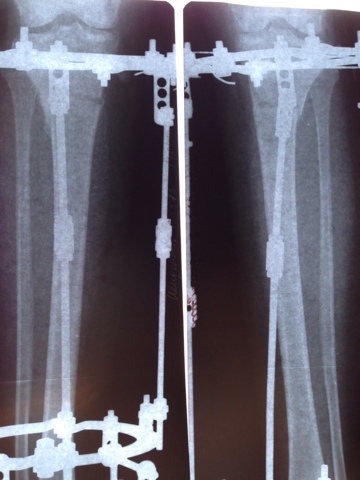

Рентген в 2 месяца с момента операции.

image-15-05-14-16-03-3.jpeg

image-15-05-14-16-03-2.jpeg